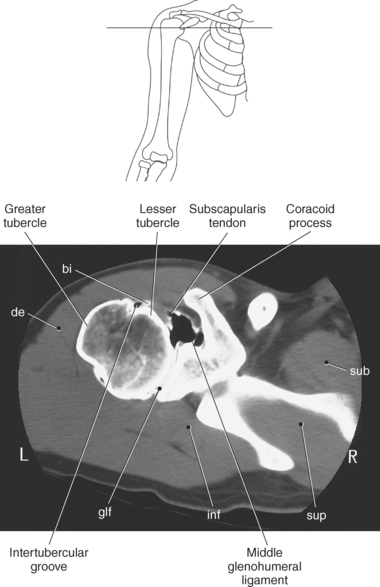

The humerus is a long bone that articulates with the scapula superiorly and the radius and ulna inferiorly. It consists of a body or shaft, a lower end (distal end), and an upper (proximal) end (Figure 9.13). The proximal end is formed by the head of the humerus. Two tubercles project from the humeral head to provide attachment sites for tendons and ligaments. The lesser tubercle is located on the anterior surface of the humeral head, whereas the greater tubercle is located on the lateral surface of the humeral head (Figures 9.12 through 9.15). The tubercles are separated by the intertubercular (bicipital) groove, which is bounded by the crests of the lesser and greater tubercles as it descends the humerus (Figures 9.9 and 9.13 through 9.15). The humerus has two necks, the more proximal anatomic neck and the surgical neck, located inferior to the tubercles just distal to the humeral head (Figures 9.13 and 9.16). In the middle of the body or shaft of the humerus, on the anterior surface, is the roughened area of the deltoid tuberosity that gives attachment for the deltoid muscle (Figure 9.13).

The edge of the glenoid fossa is surrounded by a fibrocartilaginous ring termed the glenoid labrum (glenoid lip) (Figure 9.17). The glenoid labrum is a fold of the articular capsule, which functions to deepen the articular surface of the glenoid fossa. Superiorly, the labrum blends with the long head of the biceps brachii muscle. In cross section it appears triangular (Figure 9.18). The three glenohumeral ligaments (superior middle, and inferior) are thickenings of the fibrous capsule that surrounds the shoulder joint; they contributes to the formation of the glenoid labrum (Figures 9.17 and 9.19). They extend from the supraglenoid tubercle of the scapula to the lesser tubercle of the humerus. Also aiding in strengthening the fibrous capsule is the coracohumeral ligament that passes from the lateral side of the coracoid process of the scapula to the anatomic neck of the humerus (Figure 9.19). The coracoacromial ligament is another important ligament located on the anterior portion of the shoulder. As this ligament joins the coracoid process and acromion, it forms a strong bridge, termed the coracoacromial arch, which protects the humeral head and rotator cuff tendons from direct trauma and prevents displacement of the humeral head superiorly (Figures 9.17 and 9.19). The coracoclavicular ligaments help to maintain the position of the clavicle, in relation to the acromion, by spanning the distance between the clavicle and coracoid process of the scapula (Figure 9.19). The acromioclavicular ligament, at the acromioclavicular joint, provides support for the superior surface of the shoulder (Figures 9.17 and 9.19). The transverse humeral ligament is a broad band of connective tissue passing from the greater tubercle to the lesser tubercle of the humerus, forming a bridge over the intertubercular groove for protection of the long head of the biceps tendon (Figure 9.19). The ligaments of the shoulder are demonstrated in Figures 9.20 through 9.30.

Figure 9.27 Axial, T1-weighted MR scan of shoulder.

Key: c, Clavicle; cc, coracoclavicular ligament; CP, coracoid process; ch, coracohumeral ligament; D, deltoid muscle; H, humeral head; SB, subscapularis muscle; SS, supraspinatus muscle; G, glenoid fossa; L, labrum; ss, supraspinatus tendon; b, tendon of long head of biceps muscle; IG, inferior glenohumeral ligament; mg, middle glenohumeral ligament; sb, subscapularis tendon; T, teres minor muscle.